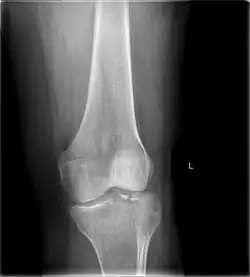

Tibial plateau fracture

A tibial plateau fracture is a break of the upper part of the tibia (shinbone) that involves the knee joint.[1] This could involve the medial, lateral, central, or bicondylar (medial and lateral).[3] Symptoms include pain, swelling, and a decreased ability to move the knee.[1] People are generally unable to walk.[2] Complication may include injury to the artery or nerve, arthritis, and compartment syndrome.[1]

Diagnosis

In all injuries to the tibial plateau radiographs (commonly called x-rays) are imperative. Computed tomography scans are not always necessary but are sometimes critical for evaluating degree of fracture and determining a treatment plan that would not be possible with plain radiographs.[10] Magnetic Resonance images are the diagnostic modality of choice when meniscal, ligamentous and soft tissue injuries are suspected.[11][12] CT angiography should be considered if there is alteration of the distal pulses or concern about arterial injury.

Subtle tibial plateau fracture on an AP X ray of the knee -

A tibial plateau fracture seen on X-ray